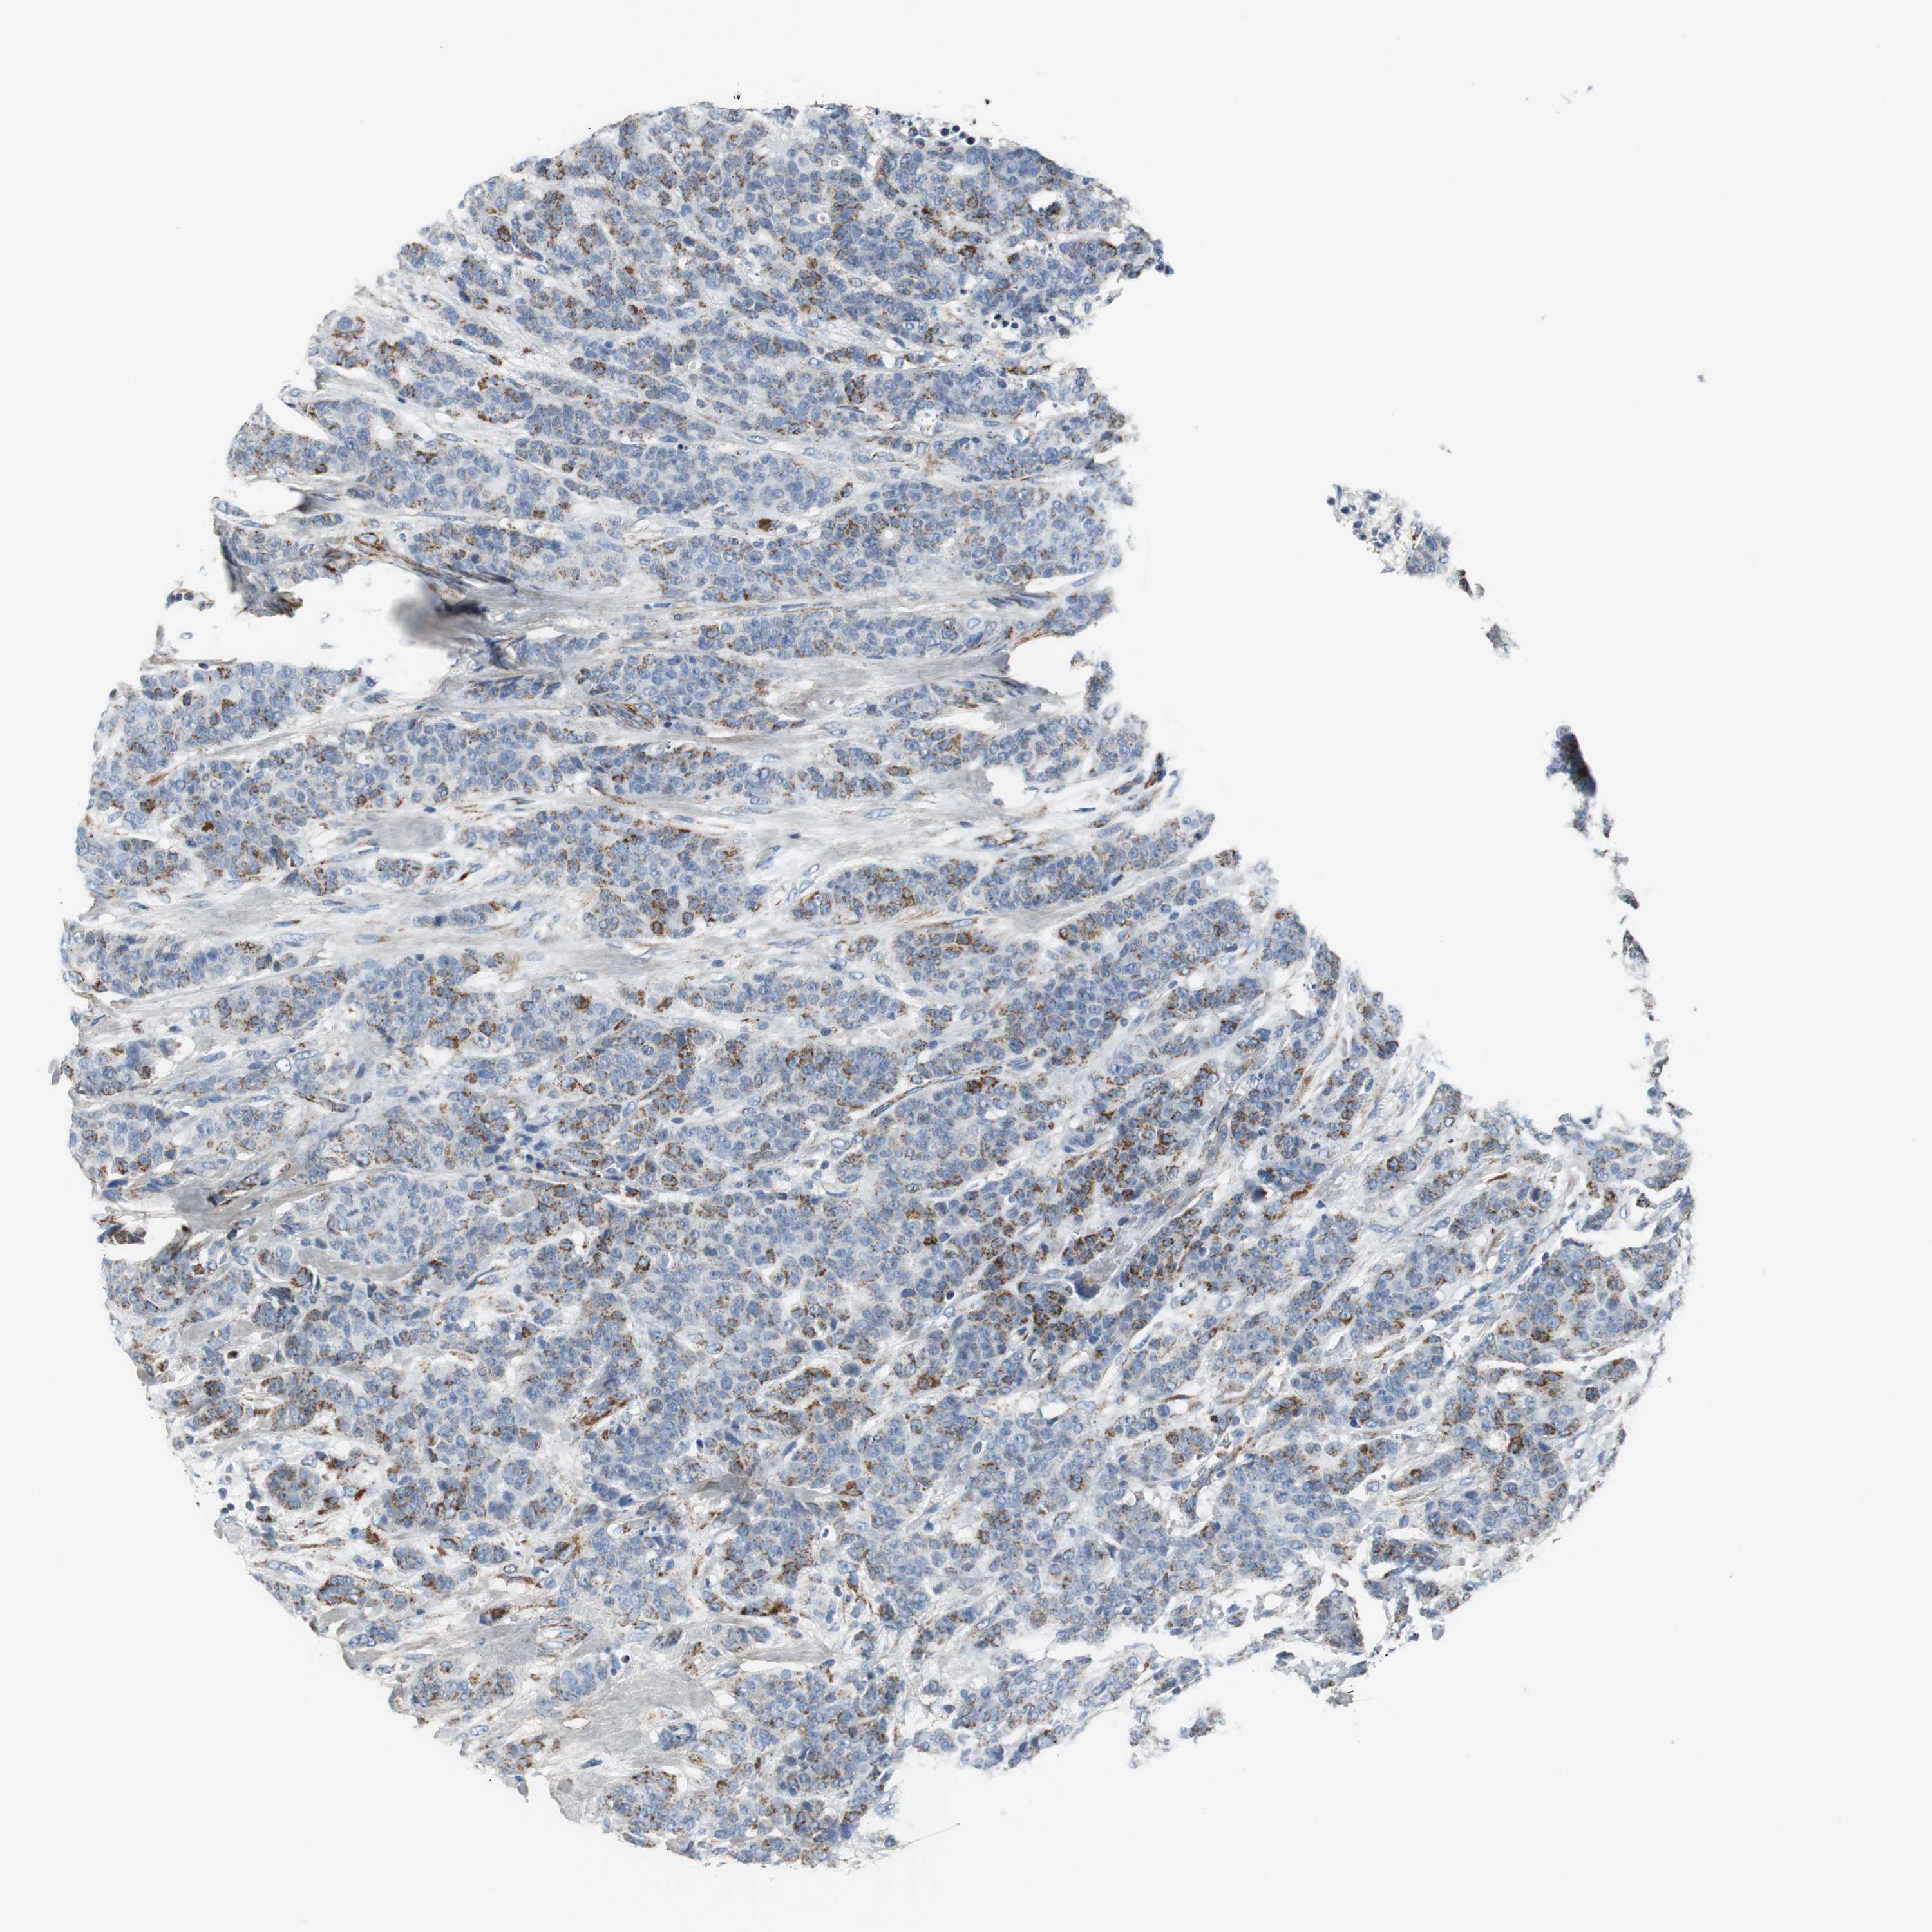

BRCA TCGA BRCA VALIDATION PROTEIN EXPRESSION

ANTIBODIES

AND

VALIDATION